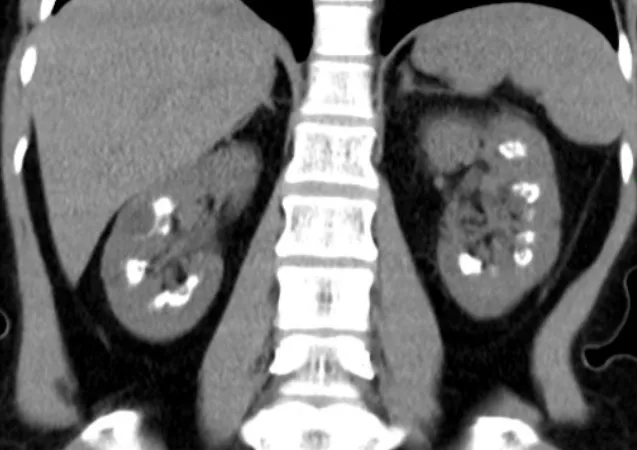

DRPAD além do Tolvaptana: Novas Perspectivas Terapêuticas nas Diretrizes KDIGO 2025

Além do tolvaptana, as diretrizes KDIGO destacam a importância de medidas não farmacológicas e abordagens complementares no manejo da DRPAD, como controle rigoroso da pressão arterial, redução de ingesta de sal e aumento de ingestão hídrica. Estudos em andamento também avaliam terapias-alvo envolvendo vias do mTOR, cAMP e inflamação. O manejo multidisciplinar permanece essencial para retardar a progressão da doença e melhorar a qualidade de vida.

Uso do Tolvaptan na DRPAD: O Que falam nas Novas Diretrizes KDIGO 2025?

As novas diretrizes KDIGO para a Doença Renal Policística Autossômica Dominante (DRPAD) atualizam os critérios de elegibilidade para o uso de tolvaptana, com ênfase na estratificação do risco de progressão rápida. O documento reforça a individualização da terapia com base em subclassificação por imagem (Mayo Clinic) e função renal. A incorporação prática dessas recomendações pode otimizar o manejo e retardar a progressão da DRC nesses pacientes.